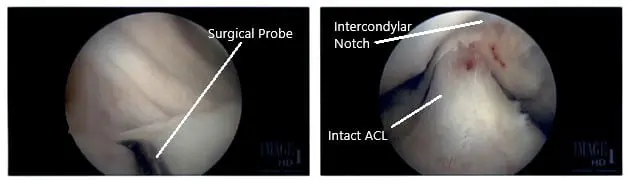

Intraoperative Arthroscopic Images of the right knee.

The decision to repair it was taken. The margins were probed using rasp and shaver. The meniscus was approximated onto the capsule and fixed using FasT-Fix Nephew curved x2. Good opposition was achieved. The sutures were cut after the notch. The all-inside technique was used. Final pictures were taken.

Finally, the scope was moved into the intercondylar area, where the ACL was found to be intact. The scope was moved to the lateral compartment, where there was faying of the posterior horn near the root of the lateral meniscus. It was debrided using shavers and punch. The scope was moved to the patellofemoral joint, which was found to be in good condition.

There was no arthritic patch over the cartilage. The scope was moved to the medial portal and the knee was re-examined again. The findings were confirmed and saved.